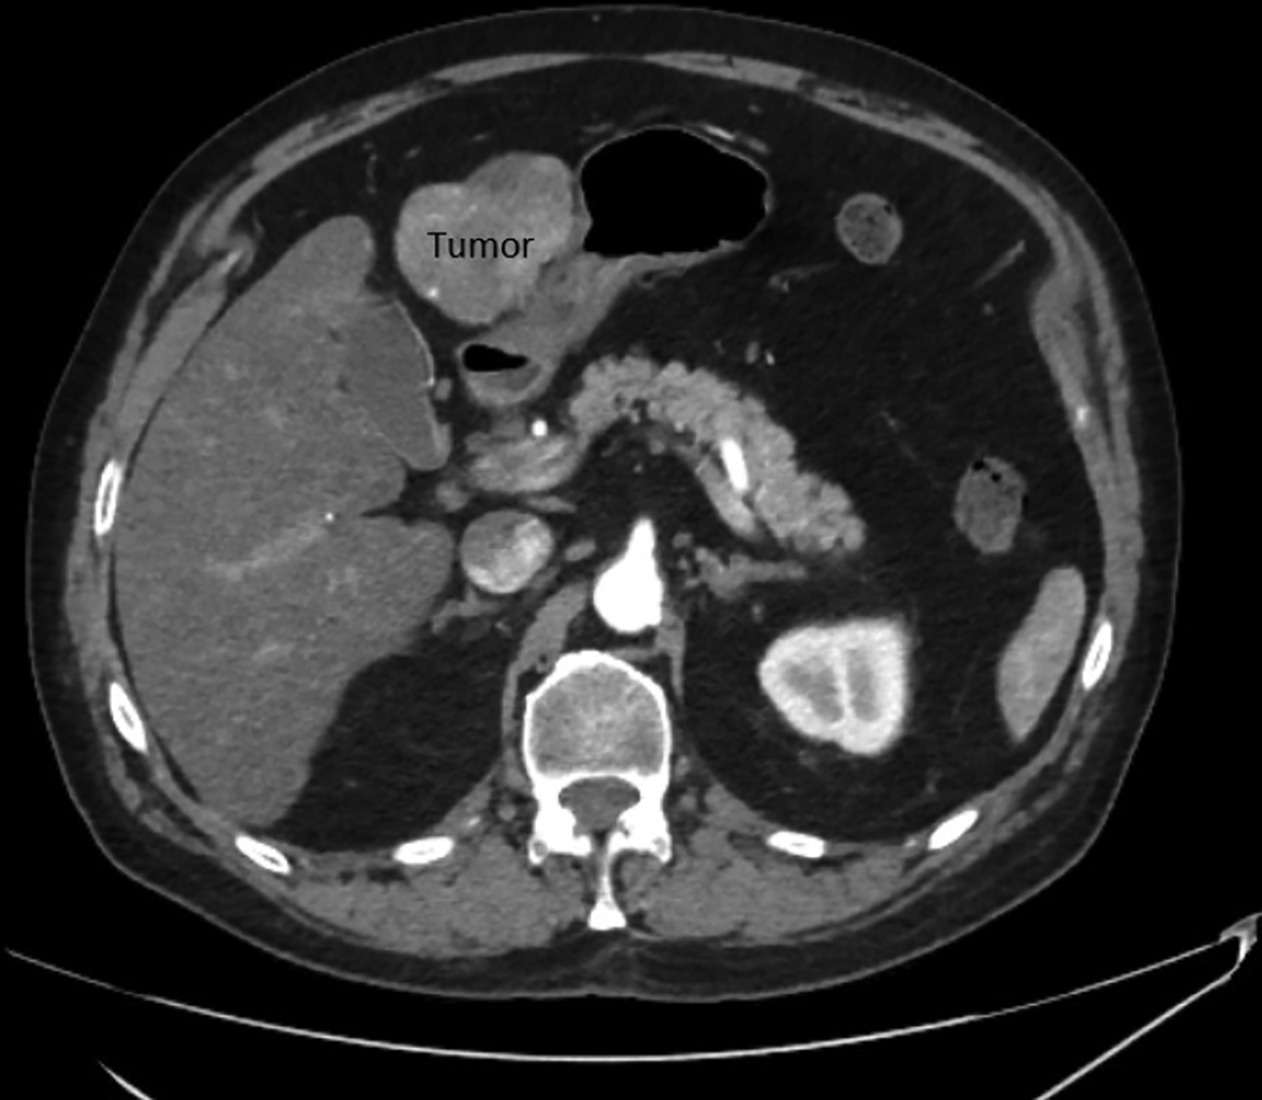

Imaging Findings

His most recent CT scan of the abdomen demonstrated a single site of active disease within segments 2 and 3 of the liver measuring up to 7 cm with an exophytic component causing abutment of the stomach (Figure 1), confirming the recommendation for MRI-guided SBRT. Given the proximity of the stomach to the tumor, endoscopic evaluation was performed within 3 months of the referral for radiation consideration and no invasion of the tumor into the stomach was observed. He underwent a planning CT and MRI simulation the following week. He was instructed to have nothing to eat for 3 hours prior to simulation and daily treatment. He received 50 Gy in 5 fractions with an adaptive workflow on the MRI linac (Figure 2). Overall time on the treatment table was roughly 1-1.5 hours, with no routine imaging post-treatment per institutional protocol. He tolerated treatment well, denying any acute side effects. All normal tissue constraints were met as per BR-0011 with the exception of the 5 cc constraint for duodenum, which we do not commonly use; however, all constraints were met based on Radiation Therapy Oncology Group (RTOG) 11122 (Table 1).